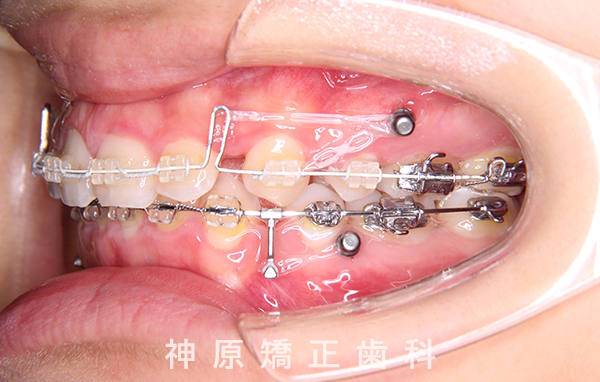

- 治療に用いた主な装置

-

上顎:唇側矯正装置

下顎:唇側矯正装置

歯科矯正用アンカースクリュー - 抜歯 / 非抜歯

- 上下左右第一小臼歯抜歯

口元の突出感を改善するために小臼歯の抜歯が必要と判断しました。抜歯スペースを活用し、前歯を可能な限り後方へ移動させるため、上下に矯正用アンカースクリューを使用する計画です。患者様とご家族に十分な説明を行い、治療ゴールに同意を得た上で矯正治療を開始しました。矯正治療の結果、側貌はE-lineに調和したバランスの良い仕上がりとなりました。